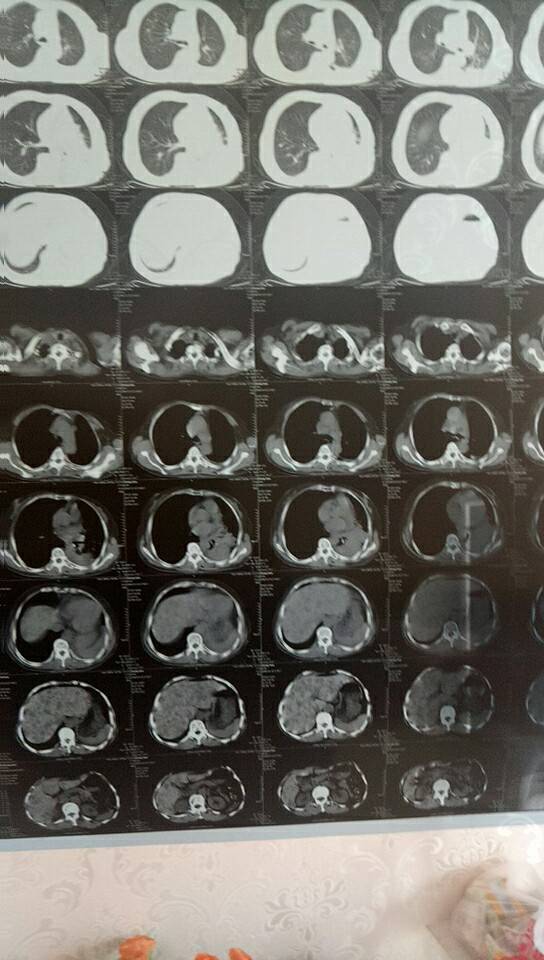

现在我妈妈主治医生要用贝伐单抗联合培美曲塞有用过这个方案的没

考虑用免疫治疗吗?我妈妈目前在吃特罗凯,没有化疗,因为她非常抵触化疗,所以耐药后我会考虑给她免疫治疗。

建议需要重新做下基因检测

我老公肺转脑,现在用的是凯美纳,女儿拿片子找北京专家看片,给的结果是凯美纳与贝伐单珠抗结合用效果好,